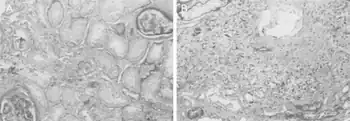

The diagnosis of this condition can be evaluated based on kidney atrophy, however even kidney status have indicated variable decrease with regards to Balkan endemic nephropathy[15]